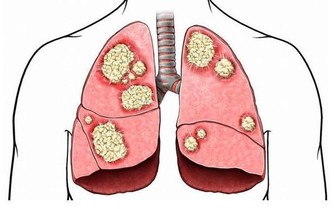

丑時肝經最旺,丑時(1:00—3:00)不眠,肝無法解除掉有毒之物,產生新鮮血液,因藏血不利,面呈青色,久之易患各類肝病。乙肝病毒攜帶者,是由於晚上經常不睡覺,人太虛弱了,也就是說秩序太亂了,病毒已經到了細胞裡了。

3、睡眠的方法